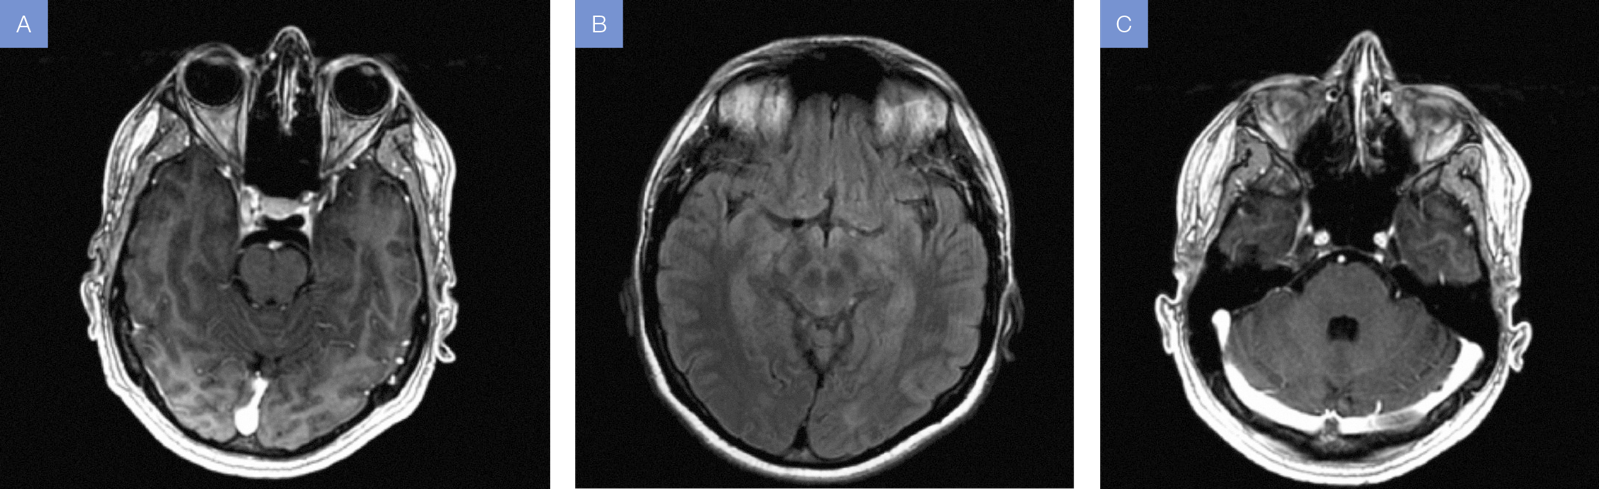

La

resonancia magnética nuclear cerebral reflejó alteración en la intensidad de

señal hacia las cisternas basales y, en menor grado, hacia los surcos de la

convexidad con incremento en la intensidad de señal en las secuencias T1, FLAIR

y leve captación leptomeníngea especialmente adyacente hacia las folias

cerebelosas; hallazgos en relación a un proceso inflamatorio leptomeníngeo en

el contexto de compromiso cerebral por malaria (Fig. 1).

Figura 1A. T1

contrastado (axial). B: T1 contrastado (axial). C: T2 FLAIR

(axial).

En

cuanto a los estudios de imagen, varios informes de resonancia magnética en la

MC han revelado cambios de señal focales o difusos en el centro semioval,

cuerpo calloso, tálamo y corteza insular; también se describen desmielinización

y microinfartos de los hemisferios cerebelosos, hiperintensidades en las

imágenes ponderadas, secuencias T2 o FLAIR secundarias a edema, isquemia,

lesión tóxica o gliosis (8).